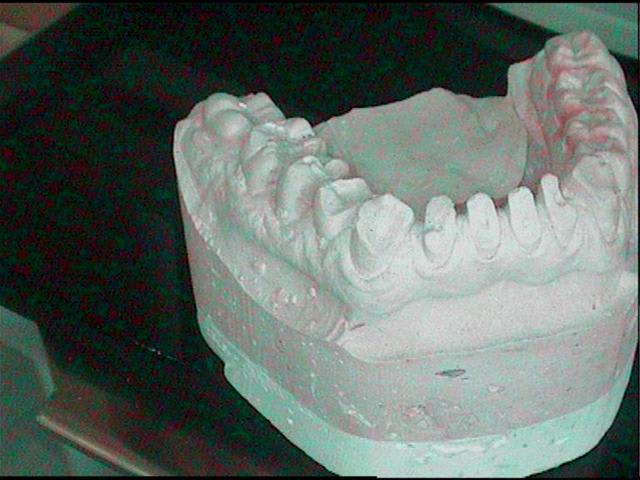

Modele initial m8gkxf - Eugenol

j'ai eu un peu le meme genre de cas adressé, mais plus simple que le tien. j'étais un peu bridé pour le traitement a cause d'un bridge quasi complet en haut